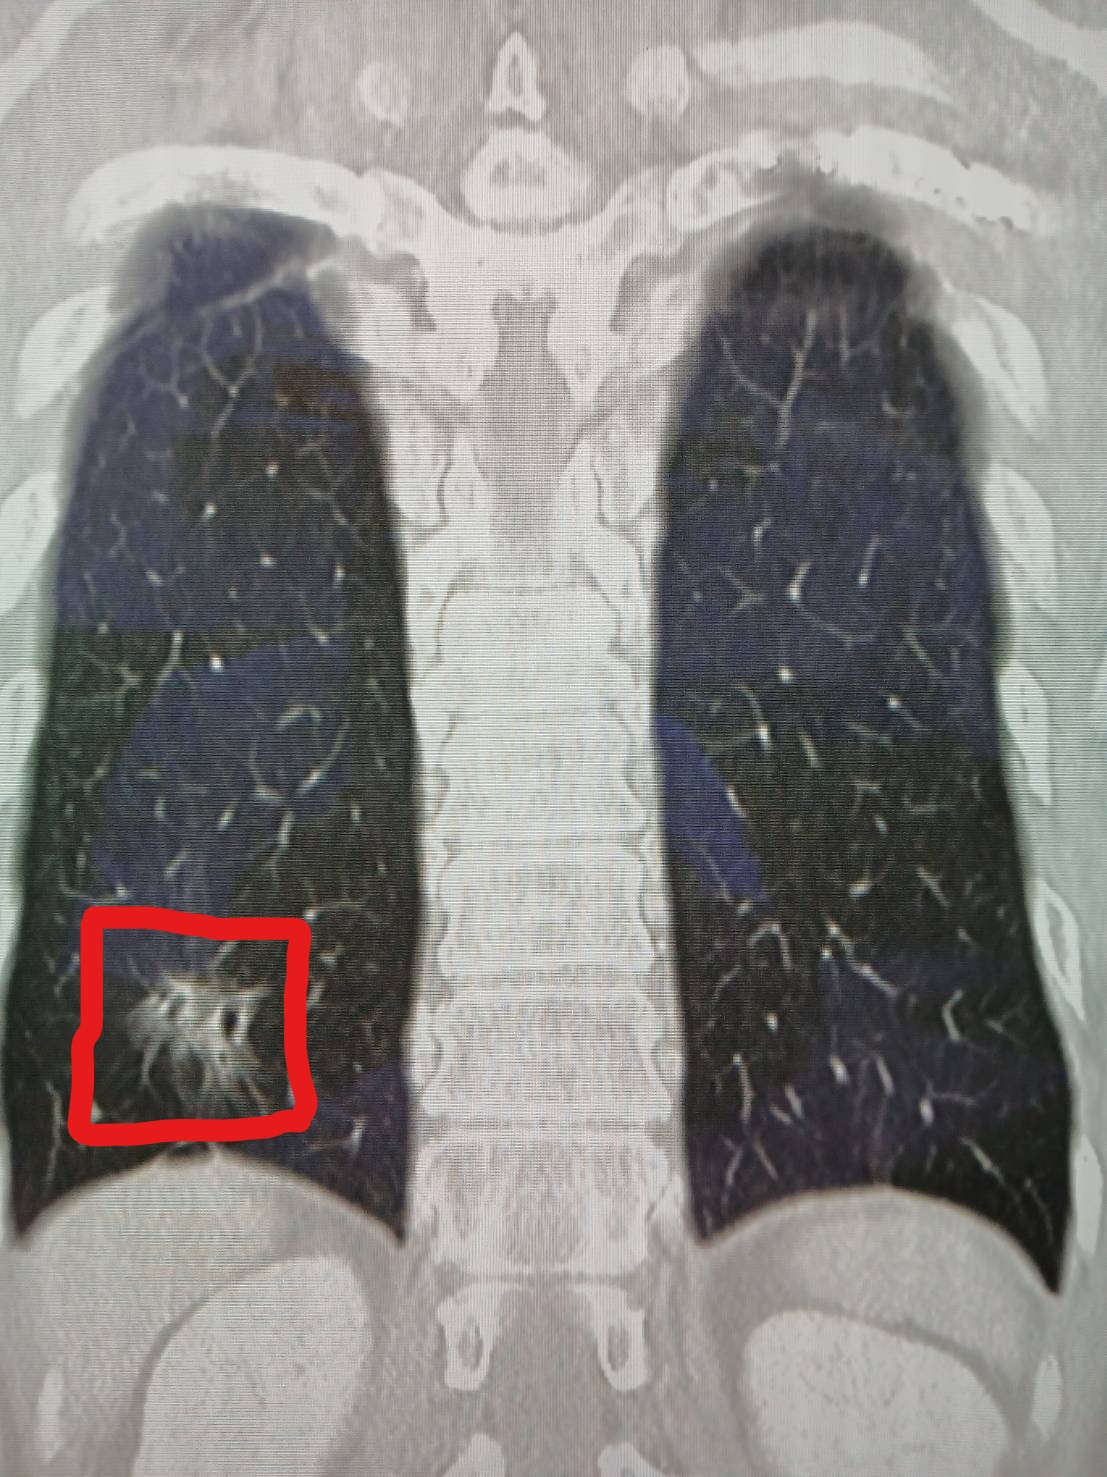

值得注意的是,在處理外傷的術前電腦斷層中,醫師敏銳發現陳先生右下肺葉有疑似早期肺癌的毛玻璃樣病灶。待陳先生肋骨傷勢穩定、三個月後回診追蹤時,發現病灶依然存在。謝志明主任隨即安排第二次「胸腔鏡微創手術」切除病灶,病理報告證實為肺腺癌第一期。

謝志明主任強調,肺癌早期幾乎無症狀,被稱為「隱形殺手」,若能在第一期發現,5年存活率高達9成以上。陳先生若非因車禍接受高階影像檢查,恐怕難以在早期發現病灶。